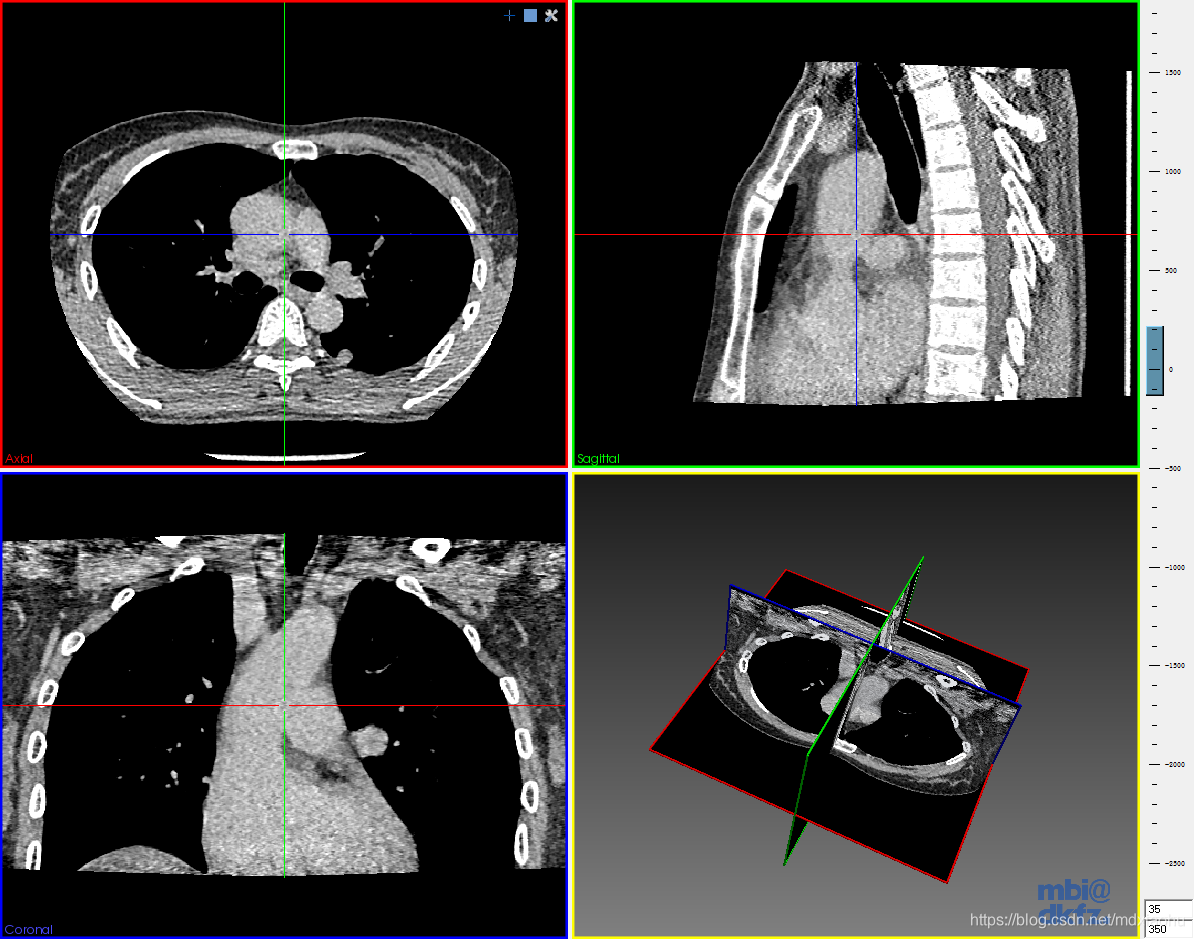

新华社惠灵顿2月27日电(记者龙雷 李惠子)新西兰一项新研究显示,可以用医学领域的计算机断层扫描(CT)技术分析古代沉积物岩芯,从而帮助揭示地震活动历史和评估地震风险。

新西兰怀卡托大学等机构研究人员近日在美国学术期刊《科学进展》发表论文说,他们利用医学CT设备对采自新西兰北部哈密尔顿盆地18个古湖泊的161个沉积物岩芯进行扫描,成功识别出火山灰层发生液化变形的迹象。

研究人员表示,这是在全球率先用医学CT技术帮助分析地震活动,该方法也适用于其他地区,这为评估地震风险提供了新工具。